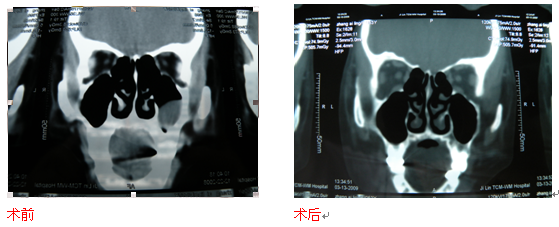

②术前仔细阅读鼻窦CT片、病历资料以及行鼻内镜检查,综合分析病情,做到术前对病情全面掌握,确立最佳手术方案,手术中精心施术,鼻内镜及动力刨削系统配合使用,彻底清除病变的同时又使手术创伤降低到最低程度,大大减轻了病人痛苦。

③术后予中西医结合治疗,拔除鼻腔填塞物后,予我科开发研制的中药鼻洗液冲洗术腔,并于内镜下换药清理,从而巩固手术效果,减少复发。这里要特别指出的是,鼻窦炎、鼻息肉是比较顽固的,因而术后需长期随访及内镜下换药清理,术后3个月到半年内会有一些类似息肉的囊泡增生,并非息肉复发,只需要简单清理就可以了。另外,鼻内镜的手术效果是以内镜下检查为准,术后鼻窦CT检查只能作为参考。